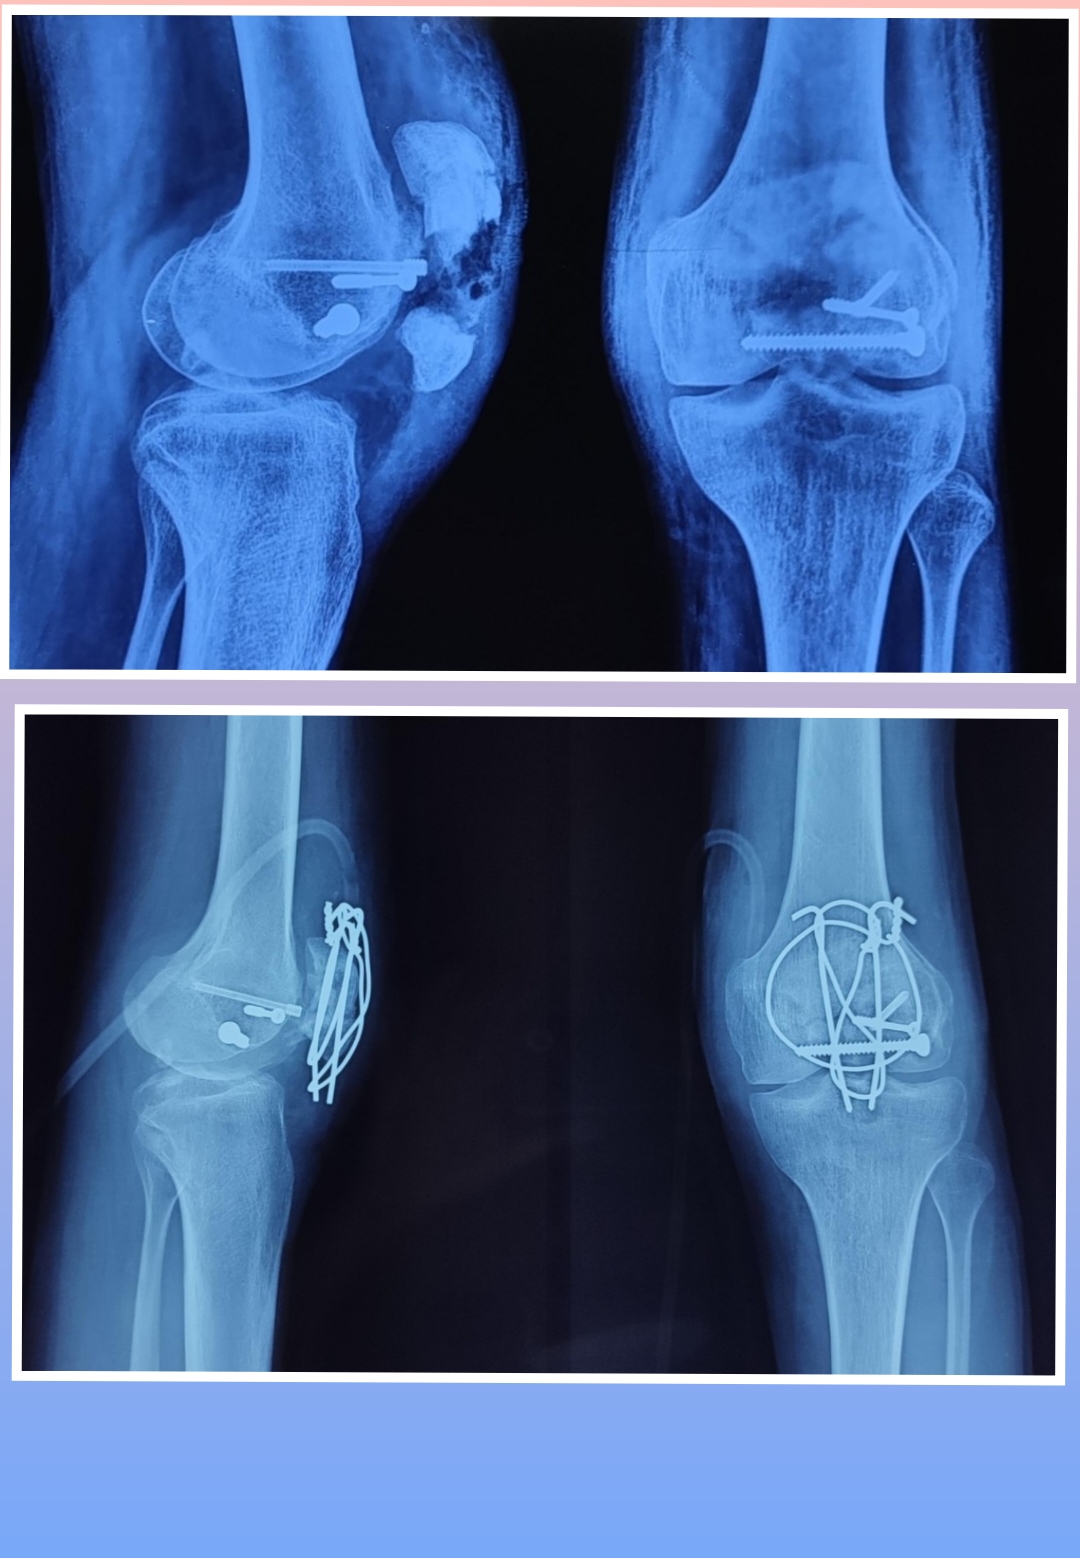

X-ray

Surgeries